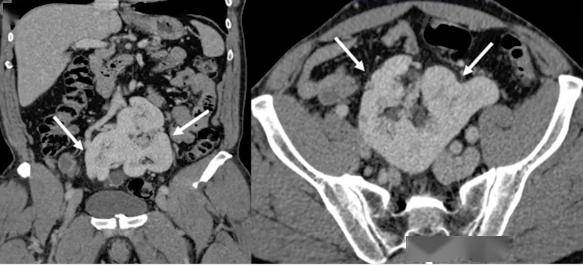

驼峰肾,马蹄肾,煎饼肾.肾脏结构异常 ct 图像,你都认识吗?